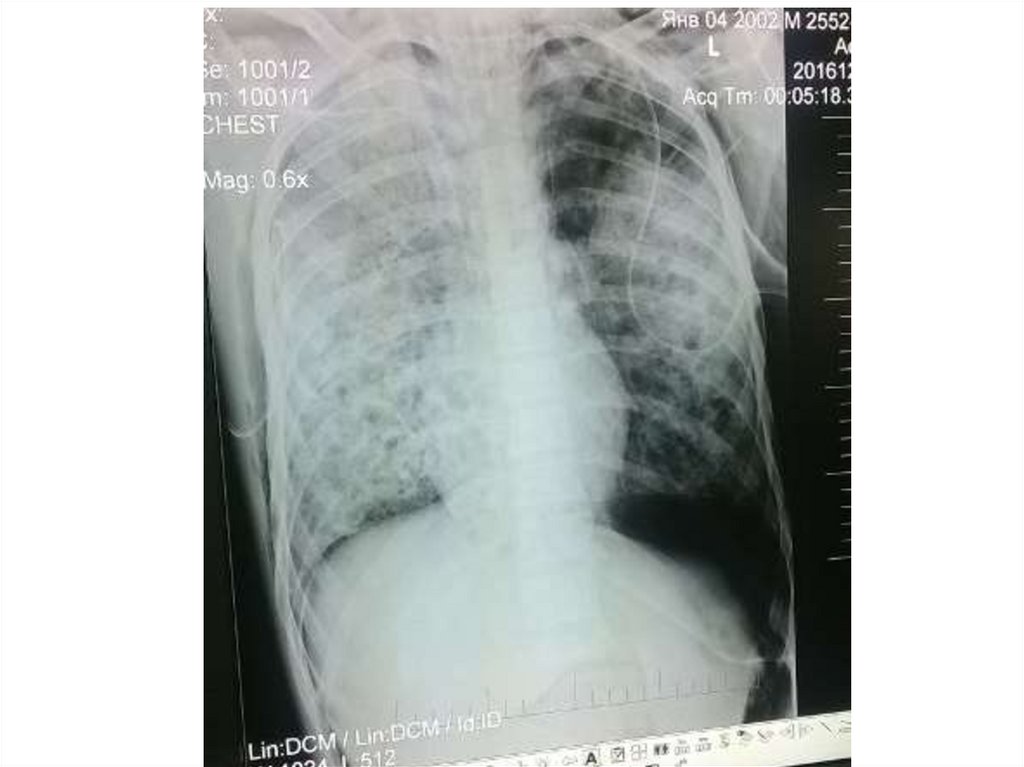

Пневмония